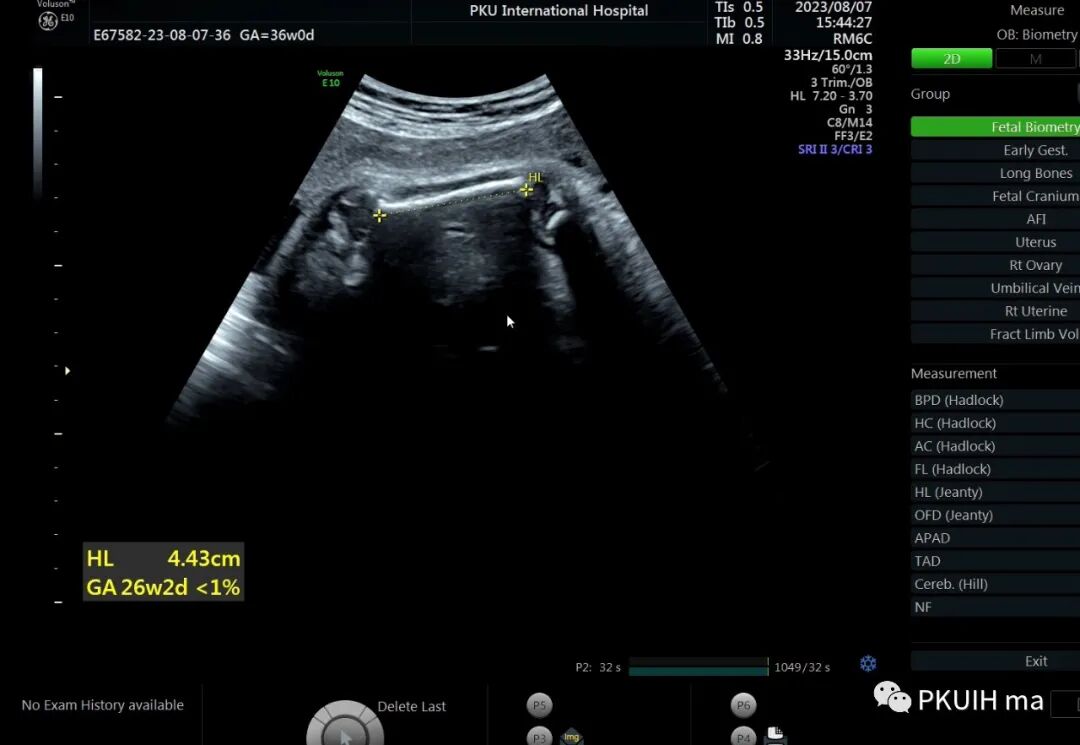

36周检查发现肢体越来越短,股骨和肱骨只相当于25-6周

头围双顶径已经大于相对孕周了,明显的头大肢体短。足底长度正常范围。